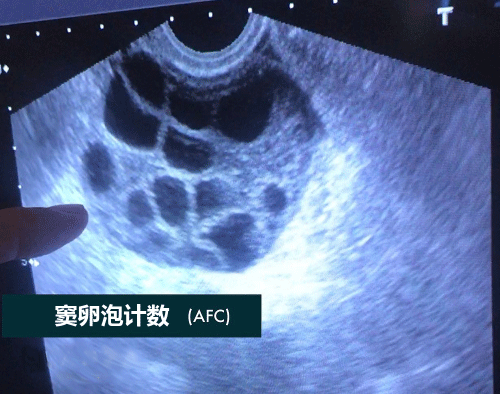

窦卵泡计数(AFC)

AFC是窦卵泡计数的缩写,是指利用B超彩超等等对卵巢的卵泡数目、大小来进行其的计数手段之一,而窦卵泡常说的是女性卵巢内直径在2-10mm的小卵泡,而通过窦卵泡计数也能够非常好的反应出卵巢储存功能等等。

女性在,最开始进行窦卵泡计数检查的时候,对于什么是窦卵泡计数都会感觉到一定的迷茫,简单的来说窦卵泡就是卵巢中成长出最为原始的3级卵泡,在阴道超声或者彩超的帮助下进行窦卵泡计数,在它们的帮助下,可以最为正确的评估与准确的计数出数量,因为女性的生育能力就是随着时间的改变而改变的,所以在医学上来说,窦卵泡计数是迄今为止最好的办法,能够在任何情况下让人知道卵巢的储存功能,以及在接受试管婴儿手术的时候也要根据这种方法来进行判断卵巢对药物反应,以增加成功率,窦卵泡计数意思就是通过这些办法计算出基础卵泡的个数,从而得到需要的结果。

窦卵泡计数数量

在经过窦卵泡计数准确的分析后,得出的结果并不是都曲尽人意的,在正常的数量上来说有一边卵巢在5-10个,不管是超出这个10个还是少于5个,很多时候表明了女性卵巢可能有一定的问题,如果高出10枚卵泡以上将会被怀疑为多囊卵巢,而如果低于5个的时候可能是卵巢功能低下引起的。

在辅助生殖医疗中,通常都会用窦卵泡计数来进行现有基础卵泡是否有发育到成熟卵泡的潜力,简单来说窦卵泡计数发现的越多,则发育到成熟卵泡的可能性也将越多,在试管婴儿及其它手术中获得的可用卵子将会更多,而也就是说到最后可用来移植的胚胎也就越多,所以窦卵泡计数试管婴儿成功率也就更高。